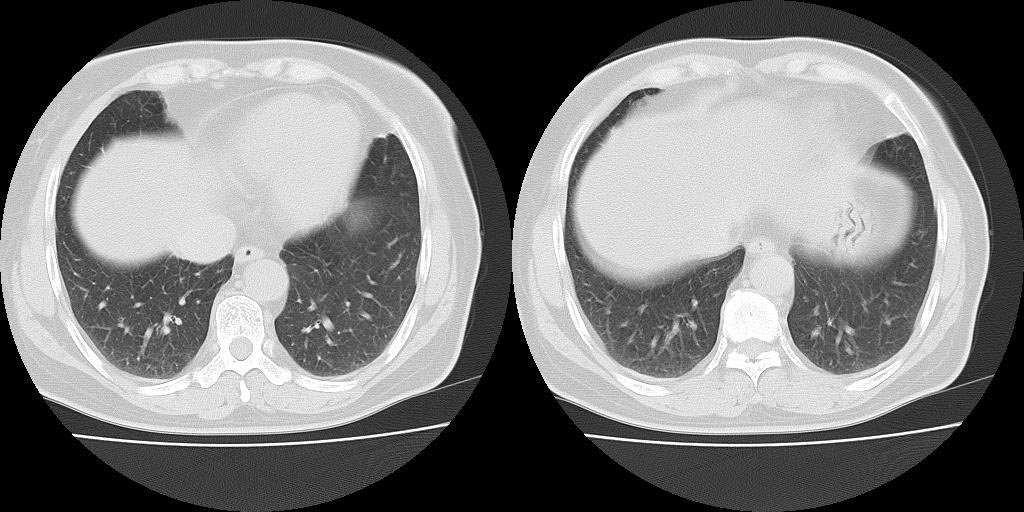

以下是引用lkc8963在2008-10-4 22:24:00的发言:[br]右下肺内基底段不规则软组织结块,肿瘤可能,建议增强鉴别于血管.